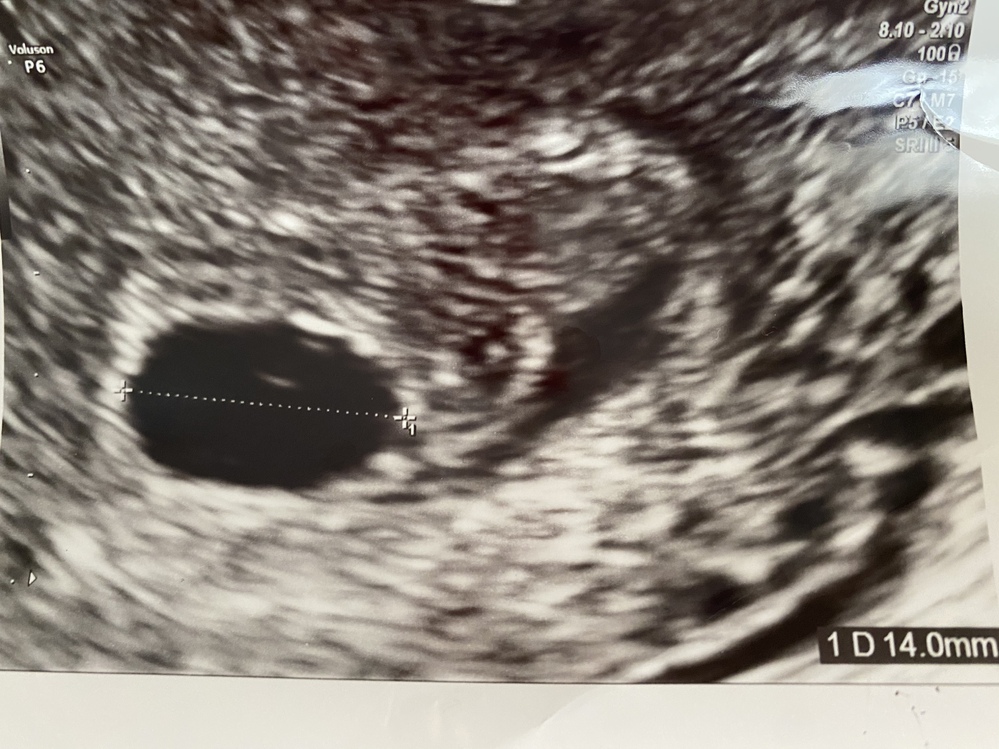

5wで胎嚢と卵黄嚢が確認できたのですが 卵黄嚢がみなさんのようにリング状で Yahoo 知恵袋